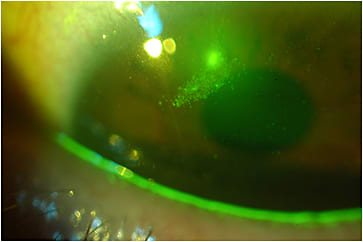

Microbial Keratitis and Epithelial Abrasions Several studies have monitored the complications associated with scleral lens wear. Nixon and colleagues (2017) present a series of case studies documenting corneal epithelial bullae and epithelial erosions (Figure 1). Of the 115 patients followed by Schornack et al (2014), three developed complications relating to scleral lens wear: one corneal abrasion during the application process, one case of microbial keratitis, and one limbal epithelial defect. Rosenthal and Croteau (2005) have also reported an incidence of microbial keratitis of 1.6%. While low, this suggests the need for careful vigilance of patients fitted with scleral lenses, as these are people whose ocular surface is already compromised.